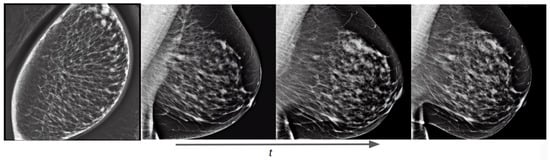

3.1.2. Joint OMI-H and VinDr Model: Concept Extrapolation

Besides allowing us to select the vendor type of the generated mammogram, the combination of both datasets permitted us to extrapolate the characteristics of one dataset into the other. This means that, e.g., the breast density of the generated Hologic mammograms can be controlled, even though this information was not available in the Hologic dataset. Figure 15 shows how the generated mammogram matches the text prompt characteristics as the training process advances, reducing the area and increasing the breast density.

Figure 15.

Training evolution of the diffusion process on a conditional pretrained model trained with both Siemens and Hologic images at epochs 1, 3, 7, and 40. The prompt is: “a siemens mammogram in MLO view with high density and small area”.